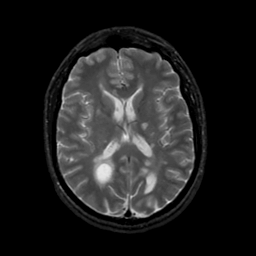

MR Study #20 October 6, 1991 -- Slice #29

[Home][Help][Clinical][Tour 1][Tour 2] Slice 29